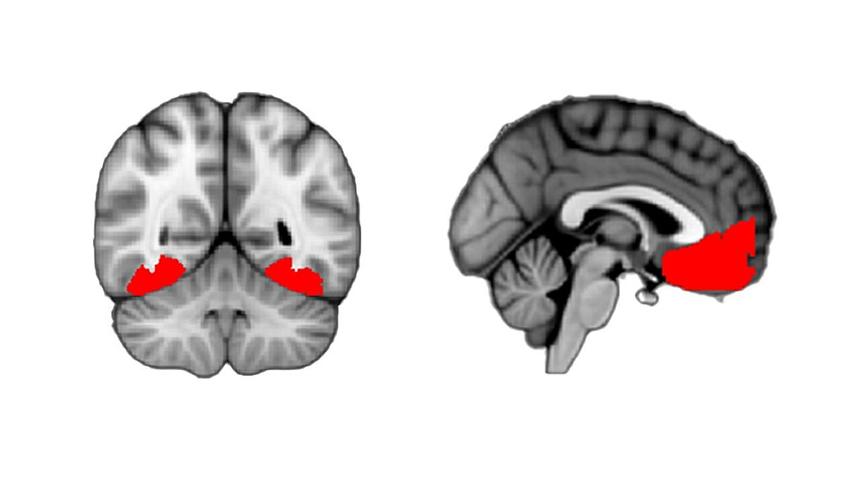

Анализ активности мозга показал, что во время любопытства возрастает активность в задней височной коре (OTC), расположенной чуть выше ушей. Этот участок мозга отвечает за зрение и распознавание объектов.

Кроме того, активными становились передняя поясная, участвующая в сборе информации, и префронтальная кора (vmPFC), отвечающая за оценку субъективных восприятий ценности и уверенности в различных ситуациях.